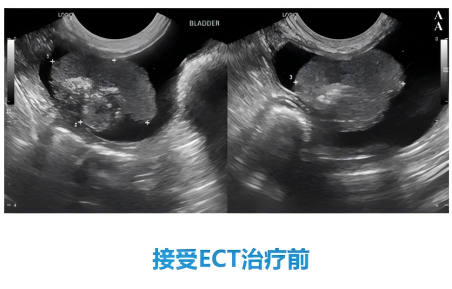

犬膀胱癌

62%的患犬实现完全缓解,24%部分缓解,治疗过程安全,无严重并发症[4];

接受治疗前

接受治疗后